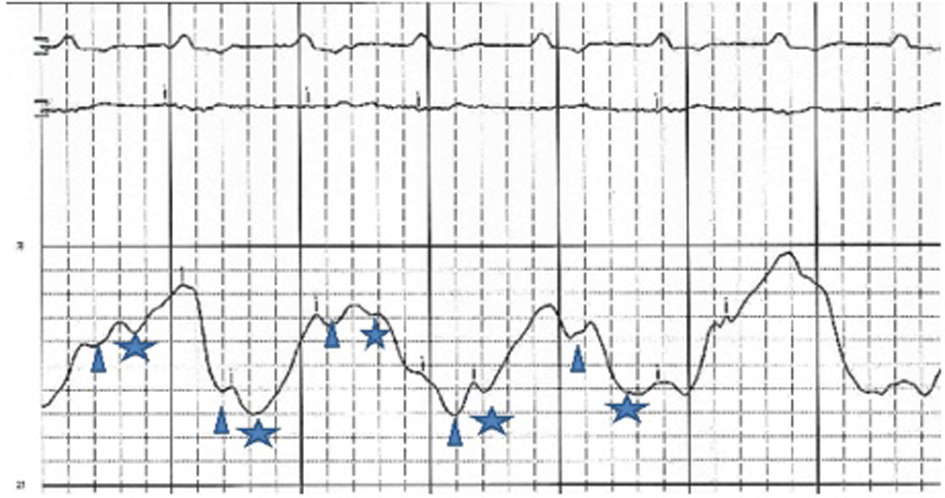

An initial complete blood count showed a mild anemia with hemoglobin of 11.2 g/dl. An anterior-posterior chest x-ray showed bilateral interstitial edema with pleural effusions. A transthoracic echocardiogram was performed and found a large pericardial effusion (Fig. 1) with tamponade physiology (Fig. 2). No intracardiac masses were noted. A right heart catheterization was also performed. The initial right atrial (RA) and intrapericardial pressures were elevated at 38 and 31 mmHg, respectively (Fig. 3). The patient underwent urgent pericardiocentesis after warfarin reversal with vitamin K and fresh frozen plasma. Approximately 1060 ml of blood-tinged fluid were removed. After pericardiocentesis there was no residual pericardial fluid assessed by transthoracic echocardiogram (Fig. 4), despite that the RA pressure remained significantly elevated at 33 mmHg. The RA tracing revealed a prominent Y descent (Fig. 5). Due to the patient’s supratherapeutic INR (international normalized ratio) and transient neurologic deterioration from sedation, simultaneous right and left heart catheterizations were not performed. The hemodynamics were compatible with effusive-constrictive pericarditis. Cytology and flow cytometry in the pericardial fluid revealed the presence of monoclonal kappa B-cells, CD 5 negative, CD 10, CD 19, CD 20, and CD 45 positive. Morphologically, the cells were consistent with large B-cell non-Hodgkin's lymphoma. A bone marrow biopsy ruled out systemic lymphomatous involvement. Positron emission tomography (PET) scan confirmed the diagnosis of primary cardiac lymphoma (PCL) showing thickening of the anterior pericardium with an standardized uptake value (SUV) of 5.0. There was no malignant uptake in any other structure such as lymph nodes, other serosal surfaces, or solid organs.

![]() Click for large image | Figure 3. RA pressure before pericardiocentesis: high RA mean pressure at 38 mmHg, X and Y descents are similar. Changes in the baseline reflect patient’s tachypnea.Δ and *represent X and Y descent respectively. |

Effusive-constrictive pericarditis is a rare form of pericardial disease that is usually diagnosed after pericardiocentesis. The hallmark is the persistence of an elevated right atrial pressure after drainage of pericardial fluid, traditionally documented by normalization of intrapericardial pressure. In our case we documented by echocardiogram with minimal residual pericardial fluid. Other classic features include reversed X/Y ratio in the atrial pressure tracing after drainage of the pericardial fluid, dip-plateau morphology in the ventricular tracings and accentuation of the interventricular interdependence. Its diagnosis is important as patients might require pericardiectomy for treatment of right sided heart failure [7-10].